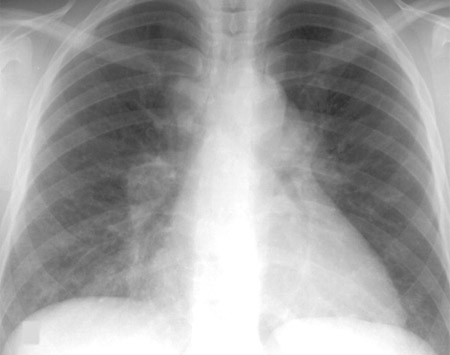

Sarcoidosis: CXR demonstrating bilateral hilar lymphadenopathy plus pulmonary infiltrates

Adapted from BMJ (2009); used with permission